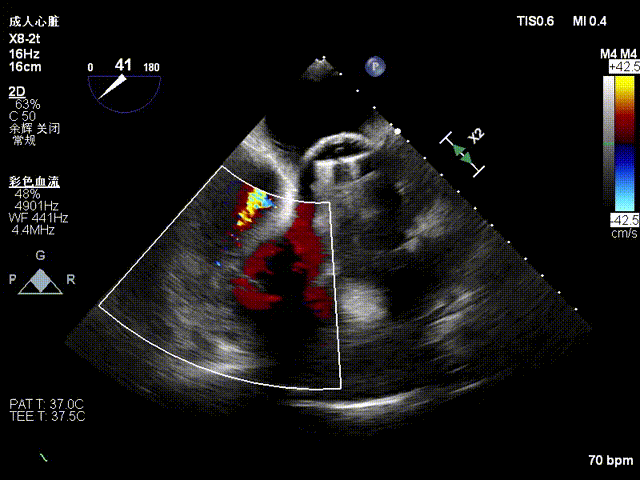

超声心动图:三尖瓣瓣环显著扩张(平均径42mm),瓣叶对合不良,TR 4+;肺动脉收缩压 58mmHg;左心室射血分数(LVEF)54%;人工二尖瓣功能未见异常。

1. 术中基线评估三尖瓣反流程度

2. 术前反流4+降至1+。